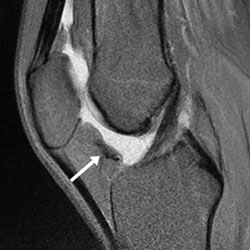

Traumatic Physeal Arrests at the Wrist

Current Concept Review

Laura Bellaire, Carley Vuillermin, Suzanne Steinman, Walter Truong, Donald Bae, Doug Wallace, Christine Ho